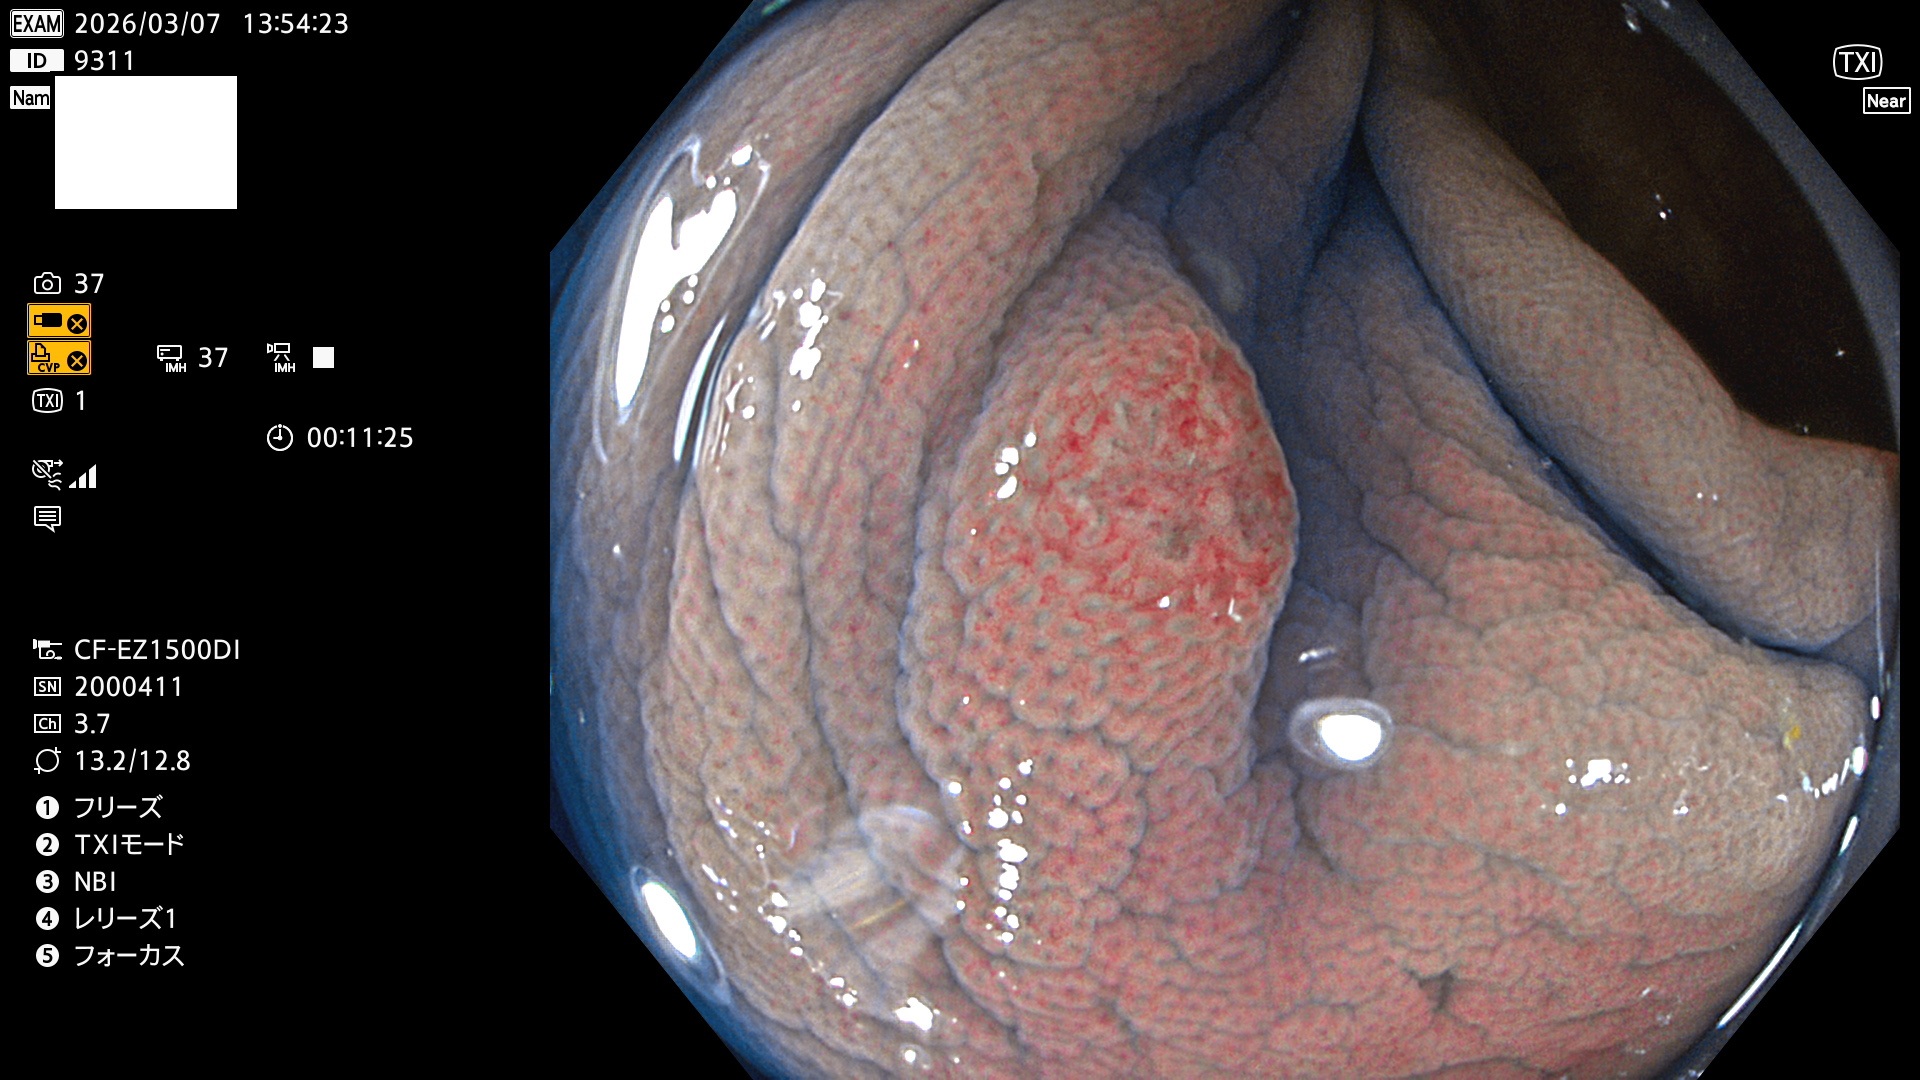

完全に平坦な物をUb、陥凹している物をUcと呼びます。Ubは認識が困難で、Ucはびらん(炎症)と紛らわしいために見落とされやすく、「内視鏡後・大腸癌」の原因になります。

専門的)Uc=De Novo癌? 内視鏡の解像度が低かった時代、このような説もありました。しかし今日の高精度内視鏡では良性の微小なUc型腺腫(APC遺伝子異常の腺腫)が日常的に見つかります。Ucこそが多段階発癌(Adenoma-Carcinoma Sequence)のMain Routeです。

毎週の検査(木・金・土・日)に発見されたUbとUc型・腺腫を、その週の日曜の夜にUPし1週間、提示します。

2026年3月5日〜3月8日の4日間(40件)9個 (Uc_ADR=9個/40人=23%)